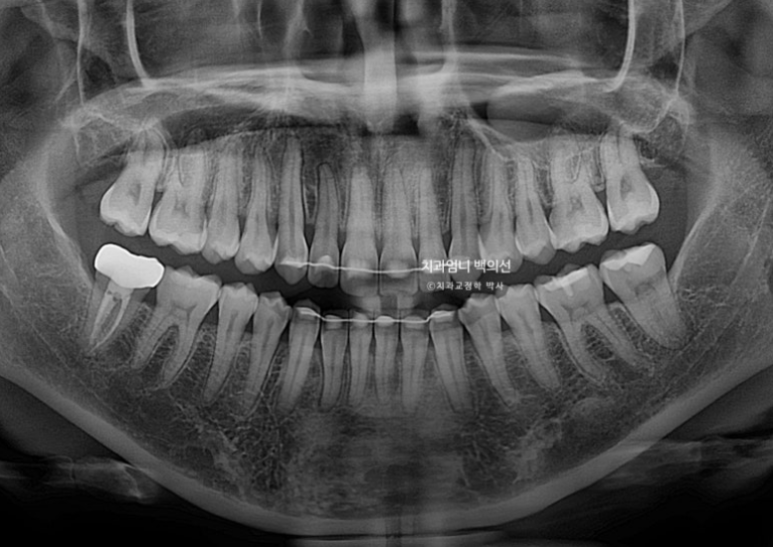

엑스레이를 찍어보면 뼈의 비대칭은 없으나 덧니때문에 위 앞니 중심선이 한쪽으로 쏠려서 비대칭감을 느끼는 상태입니다.

입천장으로 들어가있는 측절치는 아랫니와 반대로 물리는 반대교합 입니다.

치근흡수는 없고 치근평행도는 좋습니다.